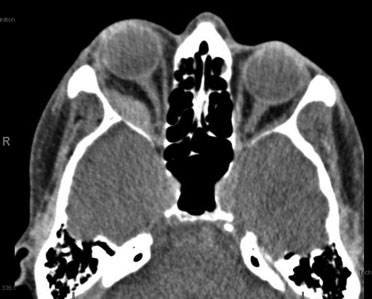

The diagnosis of RBH is clinical and depends on the history of the patient. Diagnostic clues of RBH include severe pain, double vision, difficulty opening the lids, proptosis and/or loss of vision. [6] If patients are victims of trauma, periorbital ecchymosis and eyelid hematoma may be seen. [1] Due to the severity of RBH and the possibility of vision loss, imaging modalities are usually not recommended for initial diagnostic purposes, as this is a clinical diagnosis and treatment must be prompt. [2] However, a CT scan can be useful to visualize the orbits (Figure 2), particularly to rule out concomitant injuries in cases of trauma or when the origin of the bleeding is unknown. Decrease in extraocular motility is a concerning feature of pending optic neuropathy even if proptosis is minimal and IOP is normal.

(Figure 2: CT scan demonstrating hematoma and proptosis on the right side) [10]